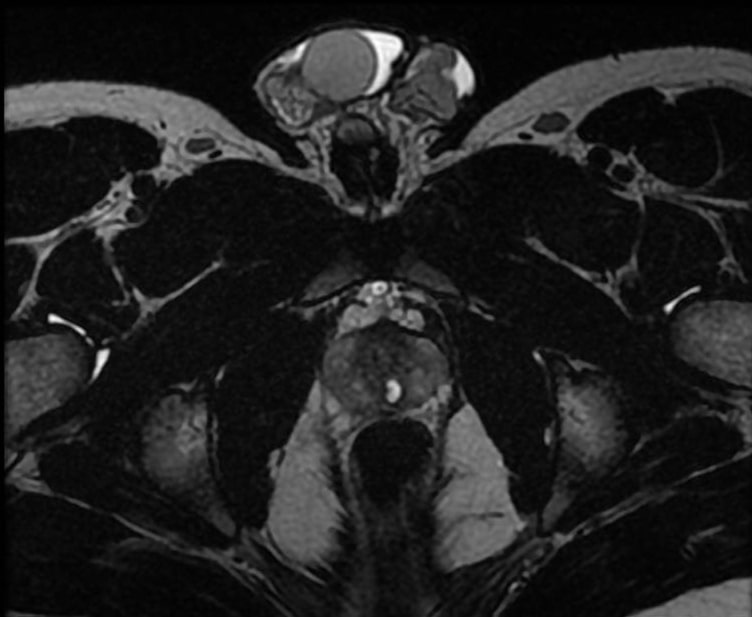

At age 16, a follow-up ultrasound identified asymmetry in the seminal vesicles, indicating congenital agenesis of the left seminal vesicle. Suspecting Zinner syndrome, an abdominal-pelvic magnetic resonance imaging (MRI) was performed, confirming left renal agenesis (Figure 1), ipsilateral agenesis of the seminal vesicle (Figure 2) along with a periurethral cyst (Figure 3) and a hypotrophic left testicle, thus confirming the diagnosis. The patient reported no abdominal, pelvic or testicular pain and no lower urinary tract symptoms. Clinical, imaging and laboratory follow-up were maintained, with the patient remaining asymptomatic throughout and retaining a glomerular filtration rate within the normal ranges.

Figure 1. Coronal T2-weighted MRI of the abdomen demonstrating agenesis of the left kidney, with compensatory hypertrophy of the right kidney.